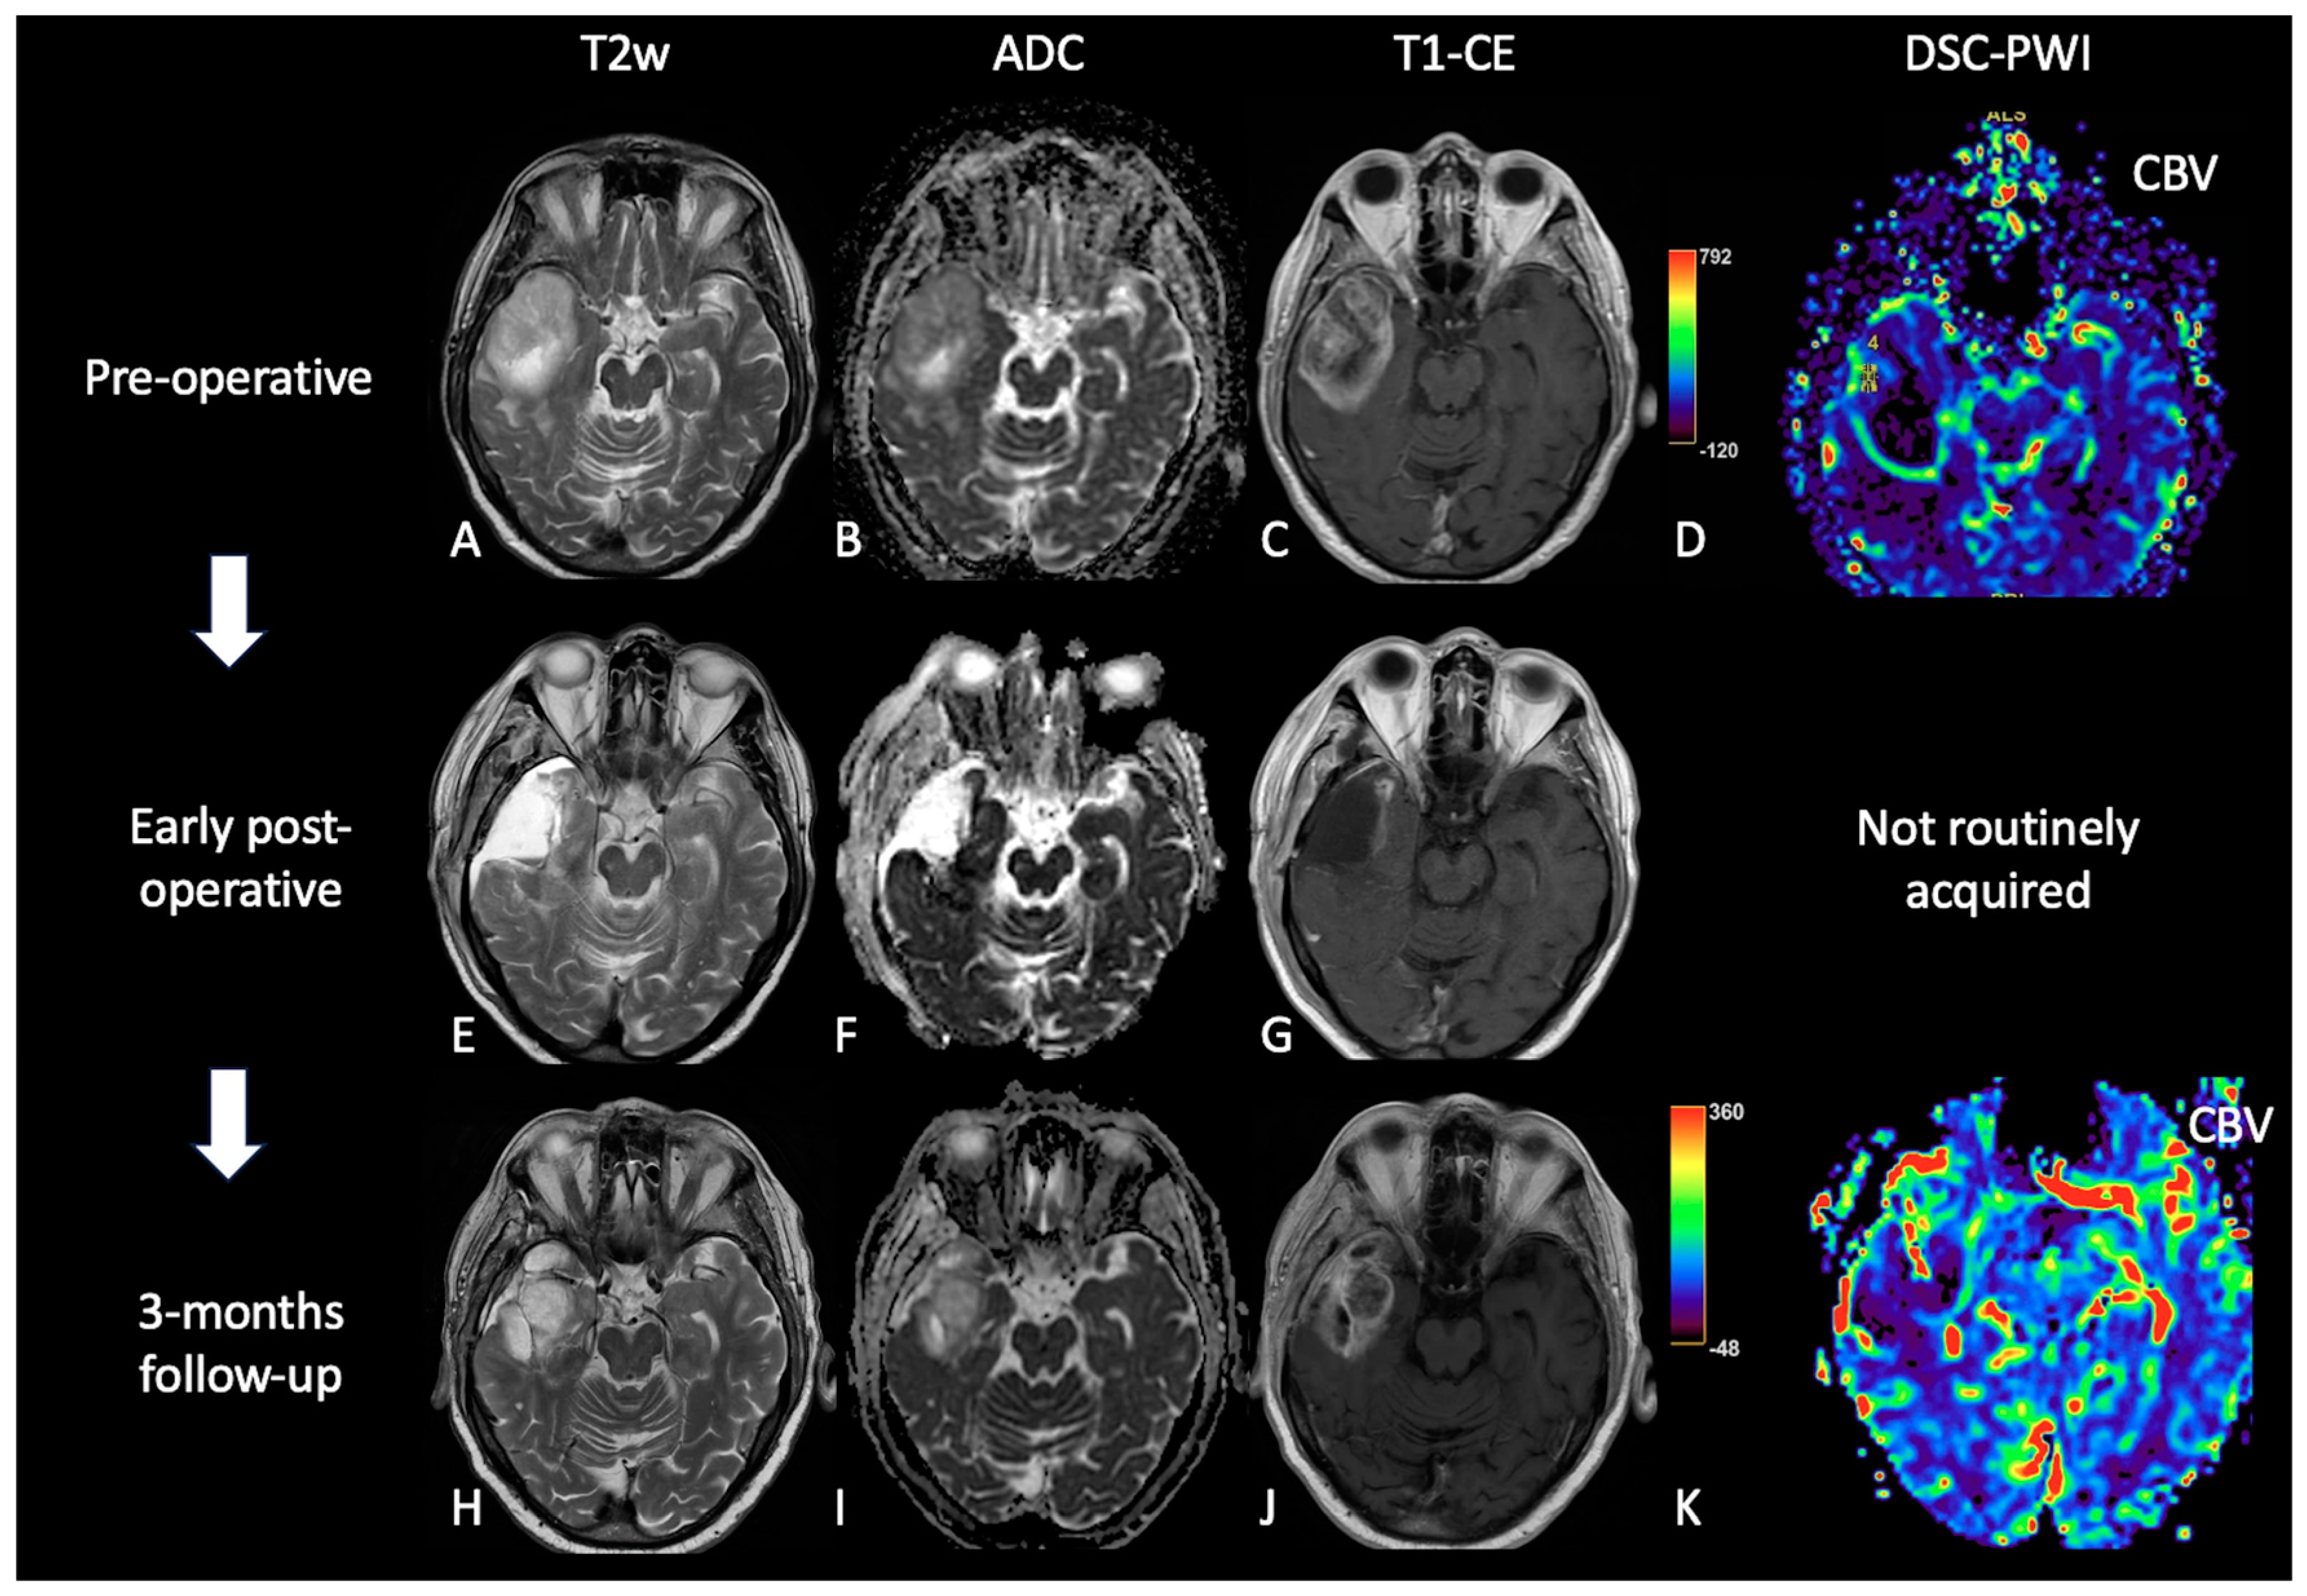

2. Early Post-Operative Imaging in Glioblastoma

3.3.2. Imaging: Conventional and Advanced MRI Sequences:

3.4.2. Imaging: Conventional and Advanced MRI Sequences

4. MRI Findings during Second-Line Therapy

4.1. Bevacizumab